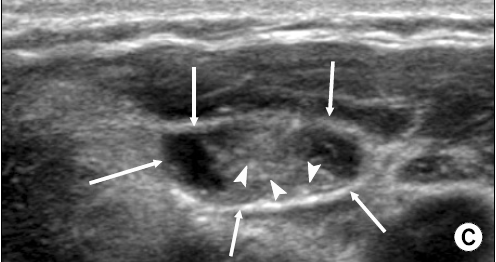

위 초음파 사진은 임파선에 갑상선 유두암이 전이된 것으로 둥그런 임파선(화살표) 안에 석회화 소견(작은 화살표) 을 보이고 있습니다.